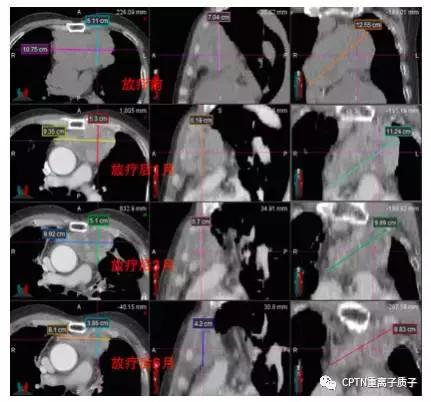

例:

不典型类癌患者,因高龄(74岁)、肿瘤巨大(11*8cm),手术风险大而拒绝手术治疗,且这类肿瘤通常对常规光子放疗和化疗均不敏感。患者接受根治性质子重离子放疗。肿瘤在放疗结束后1-9个月间持续缩小,放疗结束后15月最后一次复查时仍维持肿瘤受控状态。治疗不良反应包括轻度恶心、放射性肺炎和窦性心动过速等,放疗后3月内均明显缓解。